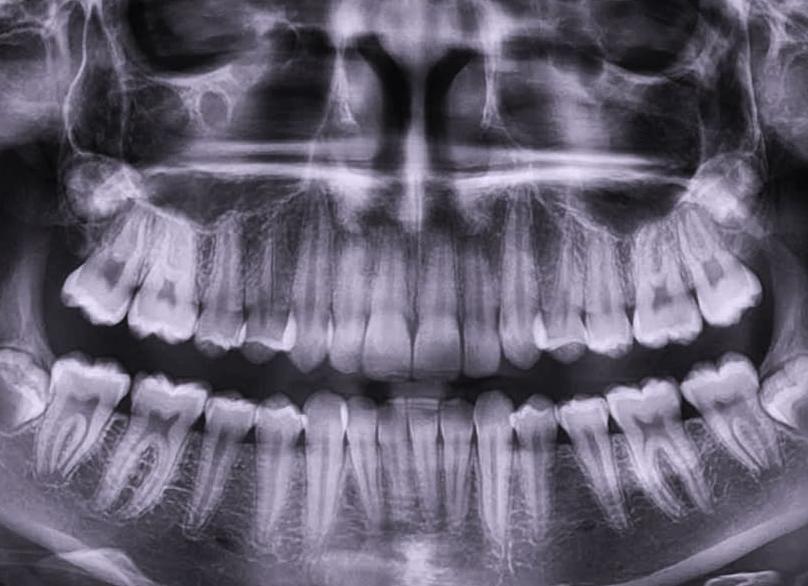

Ортопантомограмма: панорамный снимок зубов

Ортопантомограмма – это традиционный вид рентгеновского обследования зубо-челюстной системы, который также называют панорамным рентгеновским снимком. Такое название закрепилось потому, что на ортопантомограмме видна развернутая картина сразу всей зубо-челюстной системы «от уха до уха».

Таким образом, панорамный снимок зубов позволяет увидеть состояние не только всех зубов верхней и нижней челюсти, но также гайморовые пазухи и височно-нижнечелюстные суставы. Панорамная рентгенография является относительно недорогим и удобным средством диагностики, т.к. позволяет увидеть все проблемы сразу. Однако качество ортопантомограмм всегда ниже, чем у прицельных снимков или КТ.